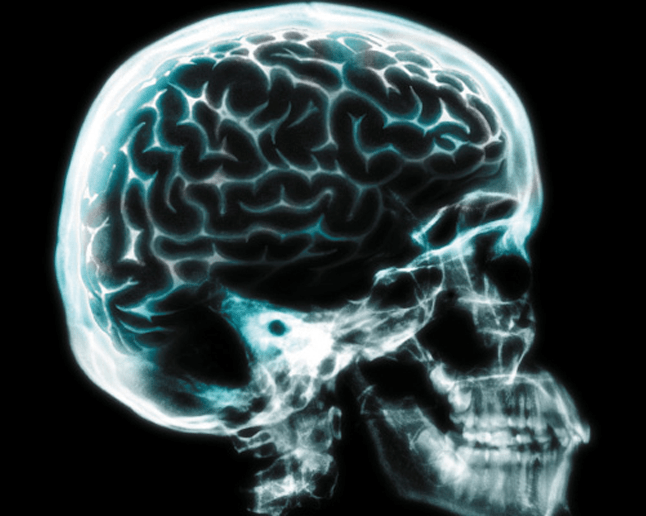

Sigara içmeye başladığınız gün beyniniz bir tekledi. Şimdi, yeni araştırmalar gösteriyor ki düzenli sigara içmek beyninizi büzüştürebilir. ‘Molecular Psychiatry”de yayınlanan çalışmaya göre beyinde anahtar rol oynayan bazı dokular zayıflayıp, incelebilir.

Araştırmada çalışan bilim insanları sigara içen kişilerin içmeyenlere oranla daha ince kortekslere (bilişsel fonksiyonlar için çok önemli olan beynin dış kısmı) sahip olduğunu gösteriyor. Hatta ötesinde, katılımcılar sigara içmeye devam ettikçe, her sene daha da fazla incelme yaşanıyor.

Korteks zihinsel hesaplamalar gibi düşünsel fonksiyonlar için kraldır. McGill University’de çalışan ve araştırmanın yürütücülerinden olan Dr. Sherif Karama’ya göre aynı zamanda dikkat ve uzamsal akıl yürütme gibi önemli fonksiyonlar için de çok önemlidir.

Daha ince bir korteks, daha ince bir bilişsel yapı demek. Alzheimer hastaları da, diğer bilişsel durumlarla birlikte bu korteks incelmelerini de yaşarlar.

Karama’ya göre “Korteks bozulursa, beyin de bozulur.” demektir.

Fakat bu korteksin kendini tamir edemeyeceğini göstermiyor. Araştırmada, eskiden sigara içen insanların bıraktıktan sonra korteks yapılarında kalınlaşma olduğu da saptanmış. 25 yıl sigarasız bir hayat sürülünce korteks normal büyüklüğüne dönebiliyor.

Beyindeki bu incelmenin sebebinin nikotin mi ya da sigaradaki diğer kimyasallardan mı kaynaklandığı tam olarak bilinmiyor. Sigara içmenin akciğerde yarattığı tahribatla alakalı olabildiği düşünülüyor. Bu durum vücudumuza oksijen alımını zorlaştırabilir ve bu hayati unsurun eksikliği kortekse zarar veriyor olabilir.